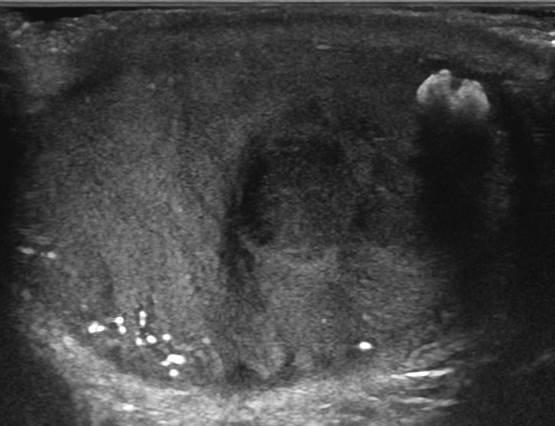

U tinh hoàn

» Thông tin: Nam giới – 28 tuổi.

» Lâm sàng: Sưng tinh hoàn.

# U tinh bào (Seminoma).